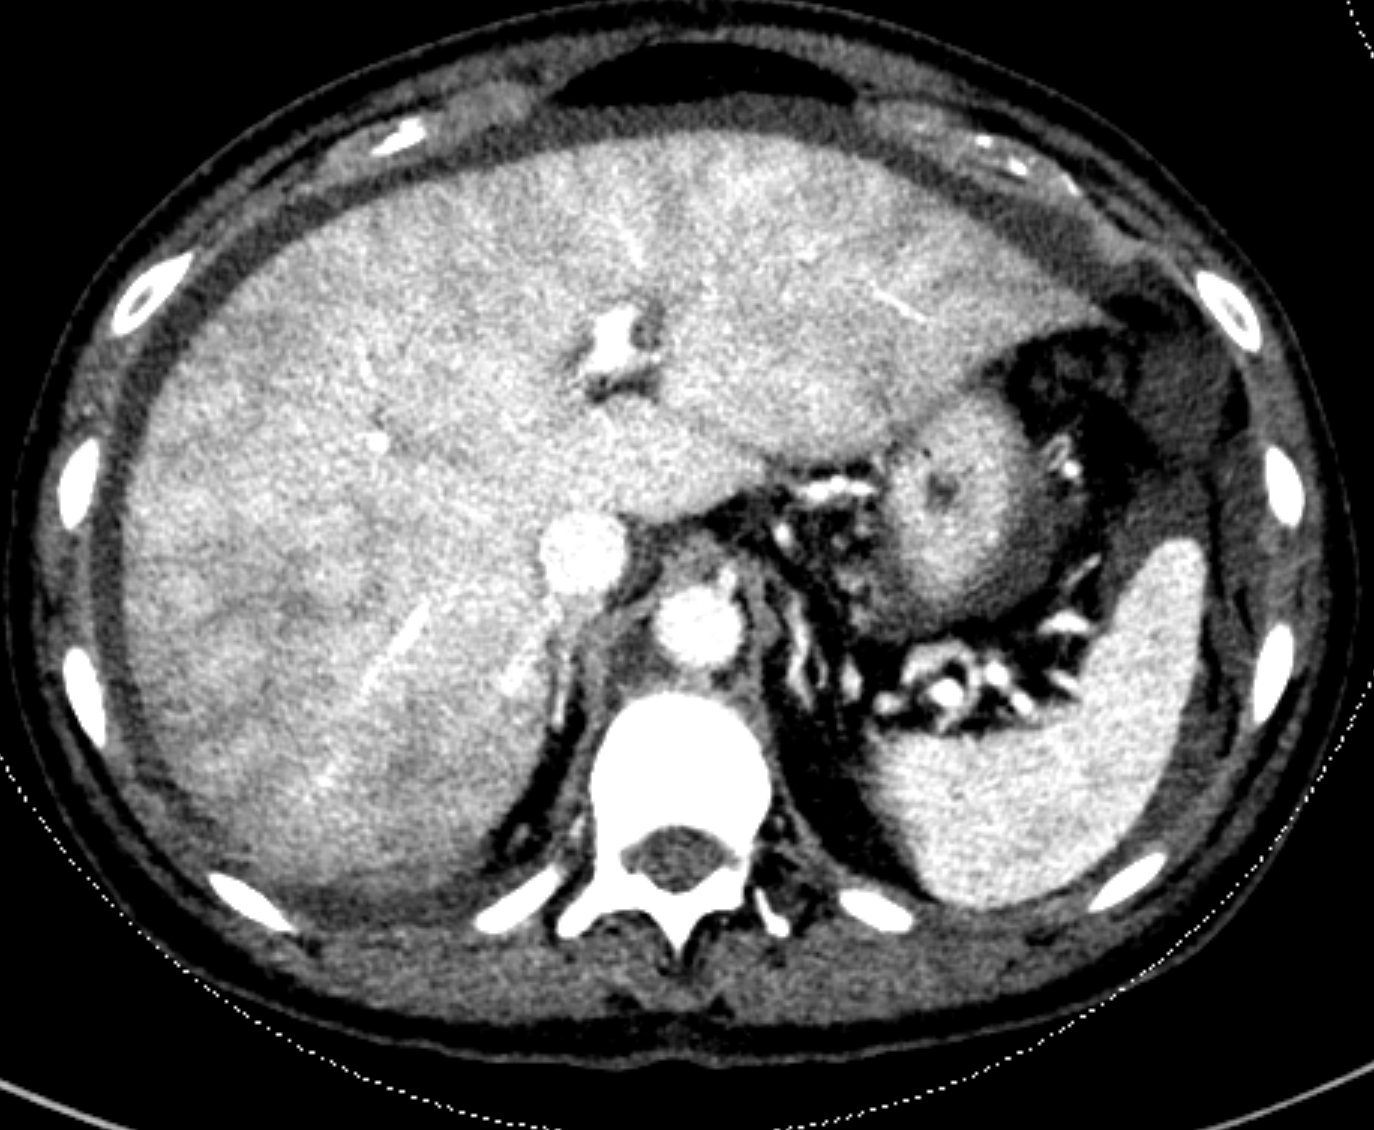

Passive hepatic congestion Radiology Case Passive Congestion Radio In day to day clinical practice, combined liver and heart dysfunction coexist due to complex cardiohepatic interaction. Congestive hepatopathy refers to liver damage caused by a variety of cardiovascular conditions that trigger passive venous congestion in the liver. The effective management of the patients is ensured after. Congestive hepatopathy refers to hepatic manifestations attributable to passive hepatic congestion, as occurs. Passive Congestion Radio.

Passive hepatic congestion Radiology Case Passive Congestion Radio Passive hepatic congestion is caused by stasis of circulating blood within the liver parenchyma. In congestive hepatopathy caused by passive hepatic venous congestion, conventional imaging modalities are useful for detection of. Congestive hepatopathy refers to liver damage caused by a variety of cardiovascular conditions that trigger passive venous congestion in the liver. The effective management of the patients is ensured. Passive Congestion Radio.